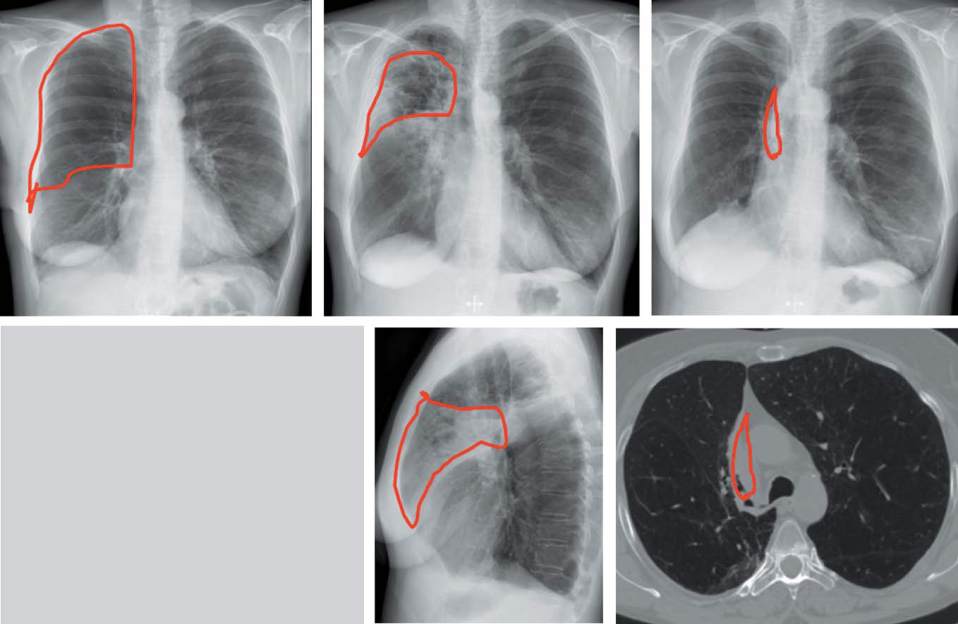

Abb. 8

Radiologischer Verlauf bei der 47-jährigen Patientin (s. Fallbeispiel). Links: vor BTVA, Mitte: 14 Tage nach BTVA, rechts: 3 Monate

nach BTVA. Lungeninfiltrat als Zeichen der lokal begrenzten Entzündungsreaktion innerhalb der ersten 30 Tage, danach Atelektasenbil-

dung. BTVA = bronchoskopische thermische Dampfablation.